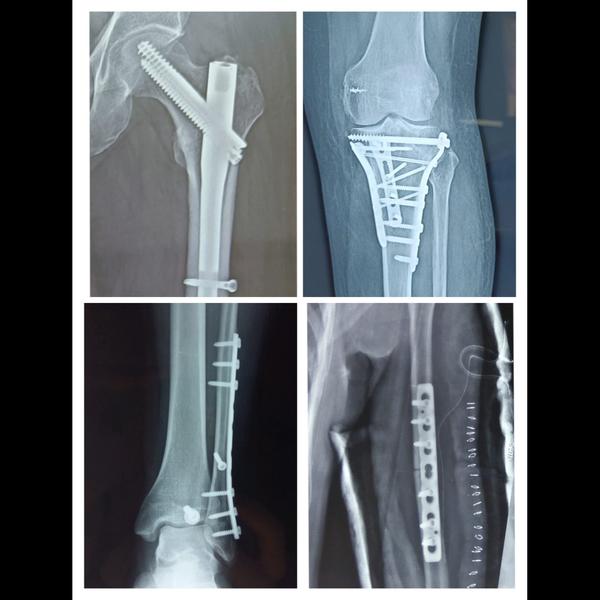

What is Effusion of the Knee? To put it simply, effusion of the knee is the escape of fluid into the tissue. This occurs when excess fluid accumulates in or around the knee joint. A small amount of fluid naturally exists in normal joints, but when a joint is affected by arthritis, for example, abnormal amounts of fluid can build up causing the knee to become swollen around the top, outside and below your knee. Water on the Knee vs. Bursitis: What's the difference? Knee bursitis is specifically explained as the inflammation of a small fluid-filled sac situated near your knee joint and around the kneecap. A bursa is the small sac that retains the fluid. The fluid that fills the bursa is called synovial fluid. Other names for water on the knee: - Effusion - Knee Bursitis - Prepatellar Bursitis - Swelling of the knee Water on the Knee vs. Swelling of the Knee: What is the difference? There are two different types of swelling: edema and effusion. Edema is swelling that occurs primarily in the soft tissues of the body. Effusion is swelling or fluid in the joint space. Symptoms of Effusion: - Swelling and redness of the skin - Joint stiffness - Difficulty straightening leg - Pain and tenderness - Knee is warm/hot to the touch - Fluid build up - Knee is large and puffy What causes fluid on the knee? The two main causes of effusion of the knee: - Arthritis Arthritis is inflammation of one or more of your joints. There are actually over one hundred different forms of arthritis. The symptoms typically include pain, swelling, and stiffness. - Injury to ligament An injury to your ligament can occur in many different ways. Ligaments in your knees include the anterior cruciate ligament (ACL), the posterior cruciate ligament (PCL), the lateral collateral ligament (LCL), and the medial collateral ligament (MCL). This can occur while on a run or other strenuous activities. The symptoms typically include pain, a loud pop, swelling, looseness in the joint, and inability to bear weight without pain. After any injury, swelling occurs because the body’s natural reaction is to surround the knee with a protective fluid. This is when effusion of the knee occurs. 5 ways to get rid of fluid on the knee: Because effusion is caused by different conditions, the best treatment process may vary depending on the person. Home Remedy It’s suggested that you use a medical knee brace to help compress the bursa and aid in treatment. Using the R.I.C.E. (Rest/ Ice /Compression? Elevation) method can help to reduce swelling and pain in your knee at home. If your knee is not improving after using this method, it is highly suggested that you call your doctor. Arthrocentesis The doctor uses a needle to drain fluid out of the knee while the knee is numbed. This method helps to relieve pain, pressure and the appearance of swelling by minimizing the collection of fluid. If needed, the aspirated fluid is sent to lab for examination. Physical Therapy Doctor may advise physical therapy depending on the cause of effusion. A Physical Therapist gives exercises and fitness activities to strengthen the knee. By keeping your leg strength, you help your knee to be stable and relieve pressure on the joint. Arthroscopy During this method, the doctor will thread an arthroscope into the knee. An arthroscope is a flexible tube with a camera at the end of it. Tools can be passed through the tube to repair damage to the cartilage and remove loose tissue, hopefully curing your knee. Joint Replacement In severe cases of osteoarthritis, the knee joint may need to be replaced with a prosthetic to relieve pain and improve function.